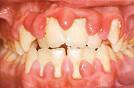

Viêm lợi là một chứng bệnh viêm phát sinh ở tổ chức lợi chân răng. Biểu hiện lâm sàng là lợi răng sưng đỏ, mép lợi tròn tù, tổ chức chân răng lỏng, dễ chảy máu, kèm hôi miệng, người bệnh có cảm giác đau hoặc ngứa căng lợi răng.

Chứng viêm lợi lâu dài có thể khiến cho lợi răng phì đại, tăng sinh gọi là viêm lợi dạng phì đại. Nếu không được điều trị có thể dẫn tới các bệnh nặng hơn về răng miệng và có thể sẽ mất răng.

Lợi có thể bị đỏ, sưng phồng lên và rất dễ chảy máu, nhất là khi đánh răng. Trong giai đoạn này, lợi có thể bị sưng tấy nhưng răng vẫn bám chắc trong lỗ chân răng.

Vào thời điểm này, lớp lợi bên trong và xương hàm bị đẩy lùi ra phía sau, tạo thành những lỗ hổng quanh răng. Những khoảng trống nhỏ giữa răng và lợi là nơi tích tụ các mảnh vụn thức ăn bị giắt vào và có thể gây ra nhiễm trùng.